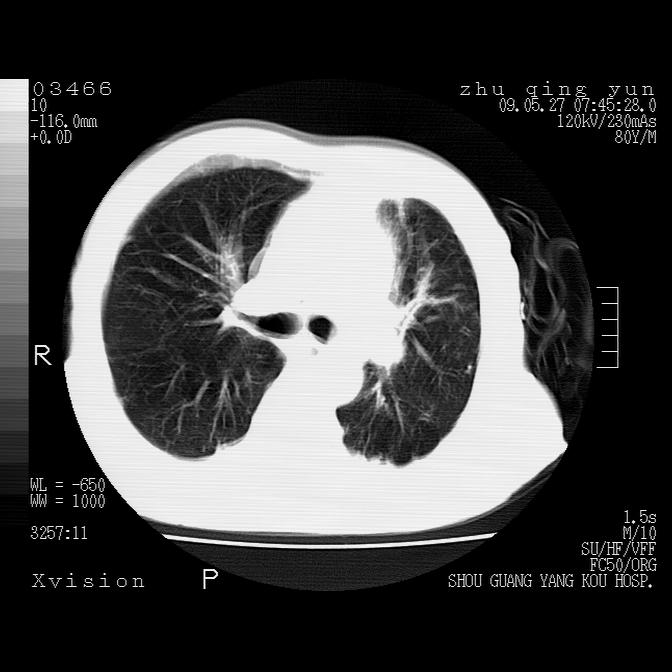

左肺下叶见多发片状及结节状病灶,左肺基底段支气管闭塞,纵隔内见多发淋巴结肿大,纵隔向左侧移位,左侧胸廓变小。应该是左肺下叶中心型肺癌,纵隔淋巴结转移,左侧肺内转移,左肺基底段肺不张,阻塞性肺炎。

1)考虑左肺中央型肺癌并左肺下叶阻塞性肺炎、不张;左胸膜腔积液、心包积液、纵隔淋巴结转移;癌肿累及左心房。2)左心室大。冠状动脉壁钙化斑。

支持以上,左肺肿块应该是周围型吧,考虑左下肺周围型肺癌伴肺内转移,阻塞性肺炎,纵隔淋巴转移,左侧胸膜及心包转移